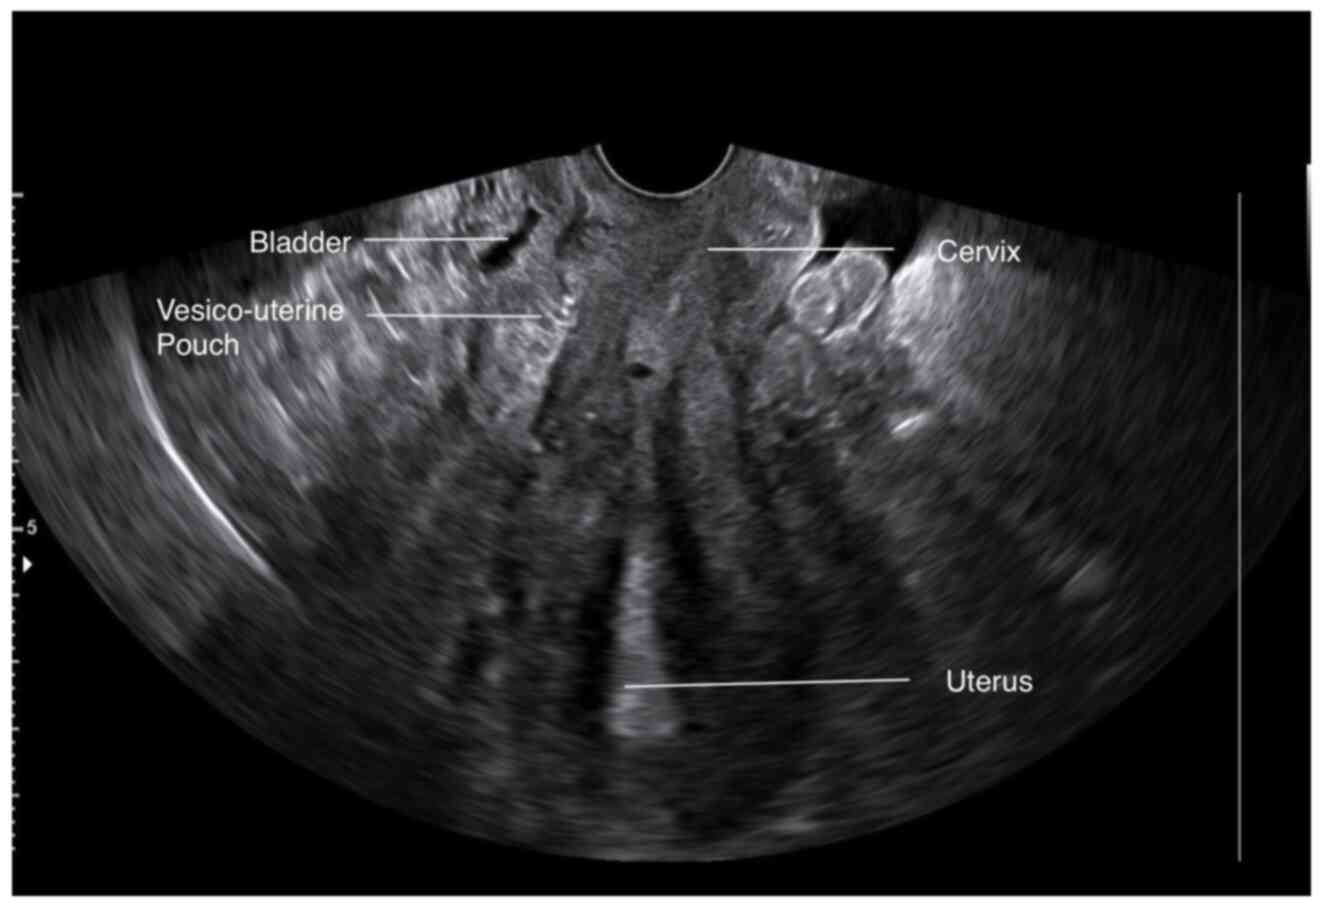

Large bladder flap haematoma following a caesarean section associated with right hydroureteronephrosis: A case report and a mini‑review of the literature

Post‑caesarean section bladder flap haematoma is a rare postpartum complication. There are currently no specific treatment protocols, at least to the best of our knowledge. In general, the failure of conservative treatment with antibiotics requires the re‑operation and surgical drainage of the haematoma. The present study describes the case of a primiparous pregnant woman who, at 40 weeks of pregnancy, delivered by caesarean section. On the 3rd post‑operative day, the puerperant, haemodynamically stable, developed febrile infection. During the evaluation, the presence of bladder flap haematoma associated with moderate right hydroureteronephrosis was found. The failure of conservative management led to the decision to perform a re‑laparotomy 1 week later. During the surgery, a large bladder flap haematoma was found with a retroperitoneal extension into the right parametrium. The surgical drainage of the haematoma and thorough haemostasis in the area of the vesicouterine pouch was performed. The patient was discharged from the clinic on the 5th post‑operative day following the re‑operation. After 2 weeks, an ultrasound revealed the complete repair of the lesions in the vesicouterine pouch and the right kidney. In the present study, a brief review of literature is also provided regarding the diagnostic and therapeutic management of patients with post‑caesarean section bladder flap hematoma.

Figure 3